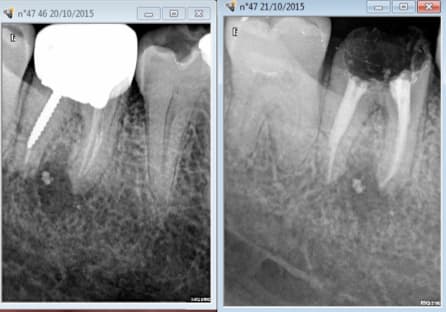

Ici inlay core 367 euros provisoire labo gratuite ( tout remboursé) et clip flow avant la provisoire gratuit. -))

Comme il y avait une pèche avant on attend 6 mois avant de faire la couronne définitive histoire que ca ne coute pas trop cher si ca foire. -))))

Apprécions la débilité de notre système de cotation de merde. -))))